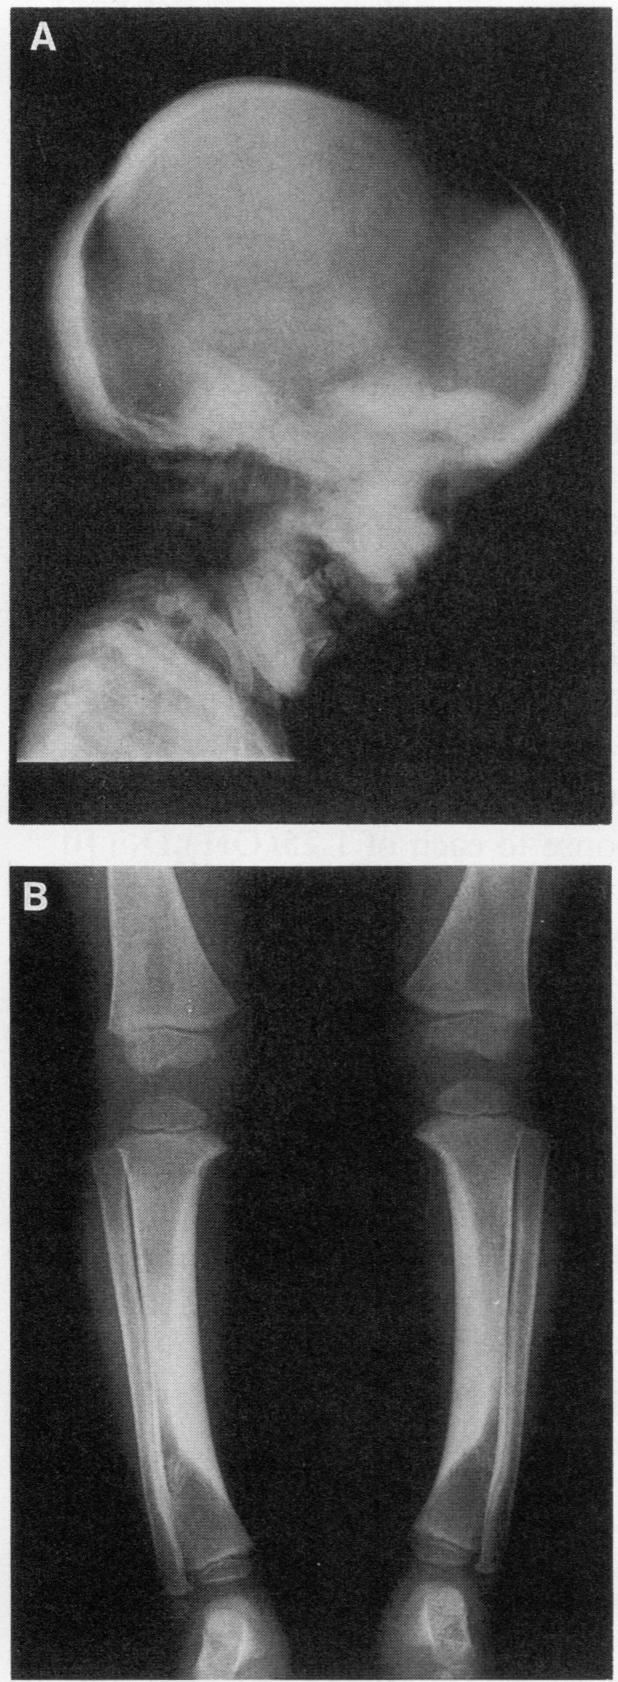

Craniometaphyseal dysplasia (CMD) is a rare craniotubular bone dysplasia transmitted in autosomal dominant or recessive form. This disease is characterized by cranial bone hyperostosis and deformity of the metaphyses of the long bones. Using osteoclast-like cells formed from patient bone marrow cells, we investigated the pathophysiology of CMD in a 3-yr-old patient. Untreated bone marrow cells from the patient differentiated into osteoclast-like cells in vitro. These cells were shown to have vitronectin beta-receptors using a specific monoclonal antibody, i.e., 23C6 (CD51), which reacts with osteoclasts in human bone biopsy samples. However, the number of these osteoclast-like cells formed from the patient's bone marrow was only 40% of the normal controls. 1,25-dihydroxyvitamin-D3, bovine 1-34 parathyroid hormone, recombinant human interleukin-1 beta, recombinant human interleukin-6, or recombinant human macrophage colony-stimulating factor significantly increased, while salmon calcitonin significantly inhibited, the number of osteoclast-like cells. However, these cells could not resorb sperm whale dentin slices and lacked the osteoclast-reactive vacuolar proton pump as evidenced by a monoclonal antibody (E11). Western blot analysis using a monoclonal antibody to pp60c-src (327) revealed that protooncogene c-src expression by the platelets of the CMD patient was comparable to the normal control. These data suggest that: (a) the hyperostosis and the metaphyseal long bone deformity in the present CMD patient might be explained by osteoclast dysfunction due to impaired expression of the osteoclast-reactive vacuolar proton pump; and (b) a protooncogene c-src was not associated with the pathogenesis of the present CMD patient.

颅骨骨干发育异常(CMD)是一种罕见的颅管状骨发育异常,以常染色体显性或隐性形式遗传。这种疾病的特征是颅骨骨质增生和长骨骨干畸形。我们使用从患者骨髓细胞形成的破骨细胞样细胞,对一名3岁患者的CMD病理生理学进行了研究。患者未经处理的骨髓细胞在体外分化为破骨细胞样细胞。使用特异性单克隆抗体,即23C6(CD51),这些细胞显示具有玻连蛋白β受体,该抗体可与人骨活检样本中的破骨细胞发生反应。然而,由患者骨髓形成的这些破骨细胞样细胞的数量仅为正常对照的40%。1,25 - 二羟维生素D3、牛1 - 34甲状旁腺激素、重组人白细胞介素 - 1β、重组人白细胞介素 - 6或重组人巨噬细胞集落刺激因子可显著增加破骨细胞样细胞的数量,而鲑鱼降钙素则显著抑制其数量。然而,这些细胞无法吸收抹香鲸牙本质切片,并且如单克隆抗体(E11)所示缺乏破骨细胞反应性液泡质子泵。使用抗pp60c - src(327)单克隆抗体进行的蛋白质印迹分析表明,CMD患者血小板的原癌基因c - src表达与正常对照相当。这些数据表明:(a)本CMD患者的骨质增生和长骨骨干畸形可能是由于破骨细胞反应性液泡质子泵表达受损导致破骨细胞功能障碍所致;(b)原癌基因c - src与本CMD患者的发病机制无关。